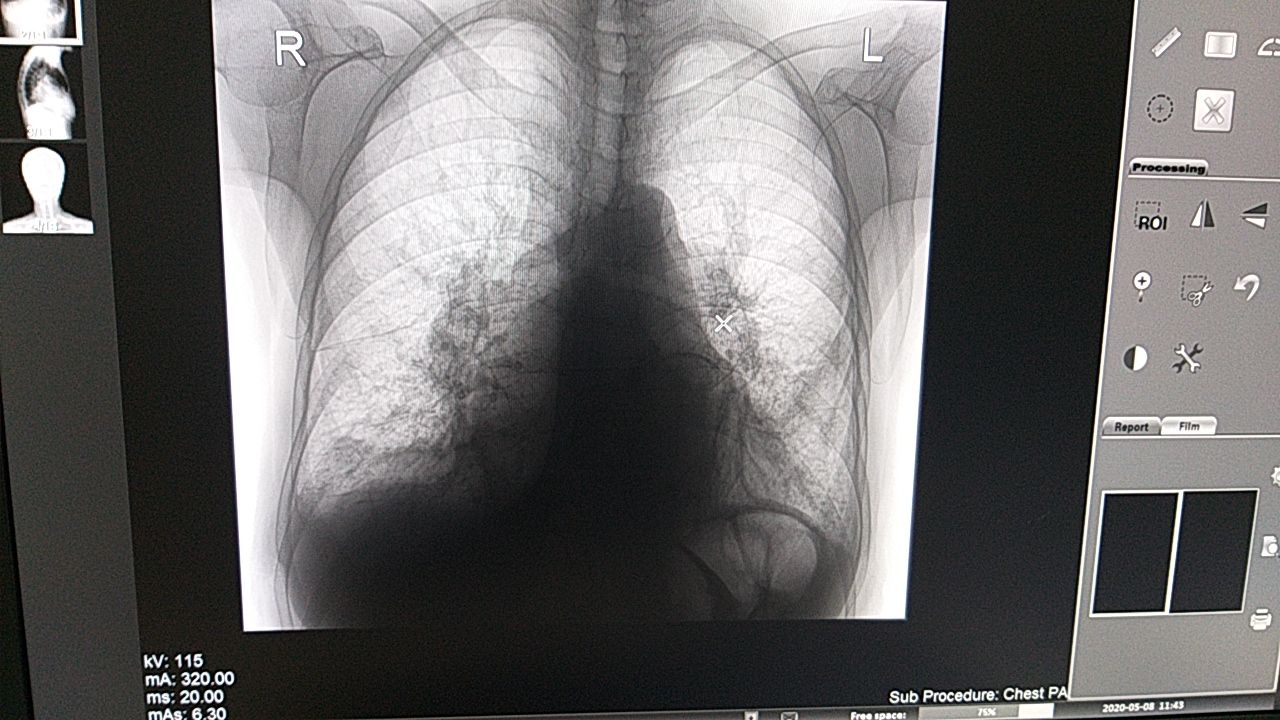

Подскажите пожалуйста начинающему врачу. У пациента температура 3 дня. Что это может быть?

Изменения по междолевой щели как можно трактовать? По плотности жир.

Либо липома с распространением по междолевой щели, либо это обычная жировая подушка перикарда

Окно немного не то, но суть вопроса понял